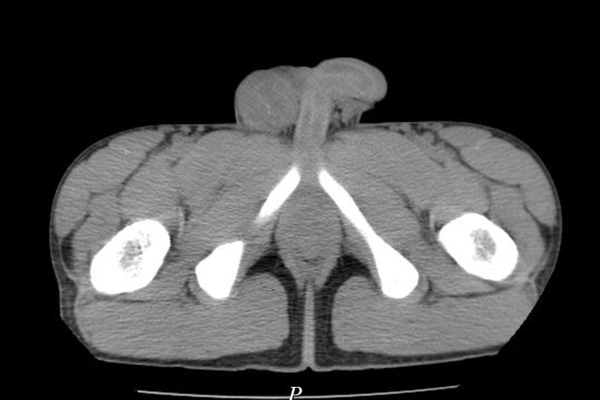

Hình ảnh các khối u đặc cứng trong bìu phải bệnh nhân

Qua kiểm tra và thăm khám, các bác sĩ nhận thấy bên vùng bìu phải có dấu hiệu sưng to, kích thước 7x8 cm, ấn đau và xuất hiện cục cứng chắc.

Làm thêm các xét nghiệm lâm sàng, bệnh nhân được chẩn đoán bệnh nhân bị ung thư tinh hoàn và di căn phổi 2 bên.